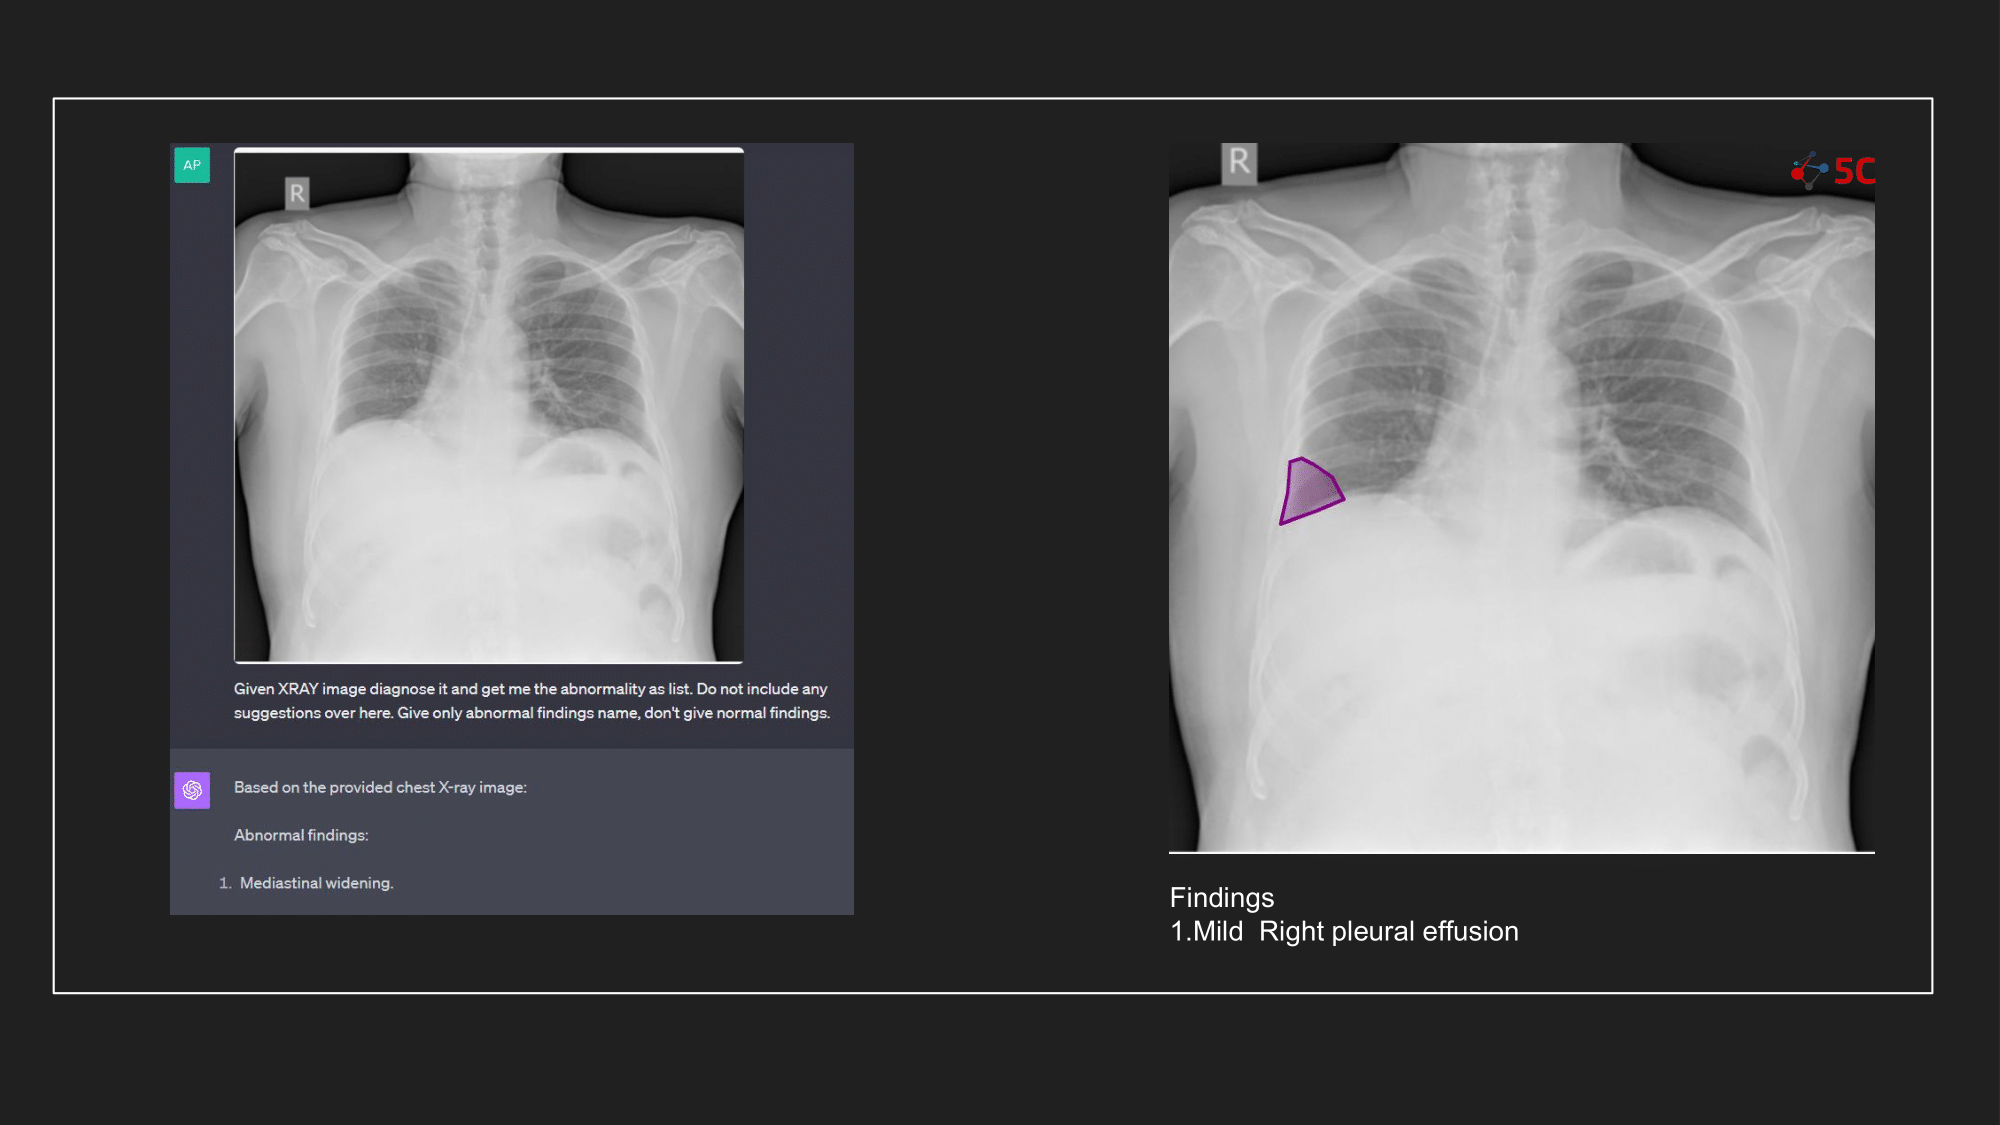

To gauge GPT-4V's prowess in detecting pleural effusion, an experiment was conducted with 10 random chest X-rays known to have pleural effusion. The XRays were sent to GPT-4V, Radiologists as well as to 5C's AI.

Presented below are the results from the experiment.

The output from GPT-4V and from 5C's AI model for the Chest XRays are provided at the end of the post.